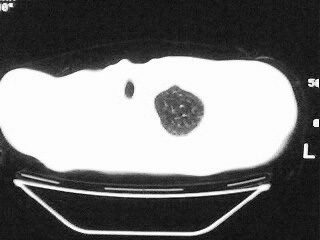

以下是引用随光逐影在2009-2-10 0:07:00的发言:[br]1)右肺放射性肺炎并节段性肺不张?请结合相关病史。2)右侧胸膜肥厚、粘连。3)心包膜增厚(或心包少量积液)。